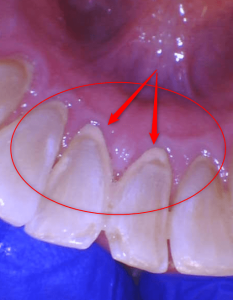

Teeth cleaning: BEFORE AND AFTER

Examine the photos below show teeth before and after cleaning by the hygienist. This tartar buildup was just two months since the cleaning. However, this patient is very prone to tartar buildup. The average person may take many more months to accumulate this amount of tartar. However, a dental hygienist can diagnose your tartar development and prescribe the frequency of having your teeth cleaned.